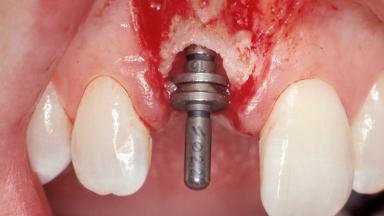

Immediate Placement of an Implant in a Maxillary Right Central Incisor Site

Type of Implants One-Piece|Reduced-Diameter

Attachment One-Piece|Reduced-Diameter

Placement Protocol Immediate implant placement

Tooth Site Maxillary incisor or canine

Socket Morphology Single-root socket

Socket Integrity Sufficient, with intact bone walls

Bone Volume Sufficient, with intact walls